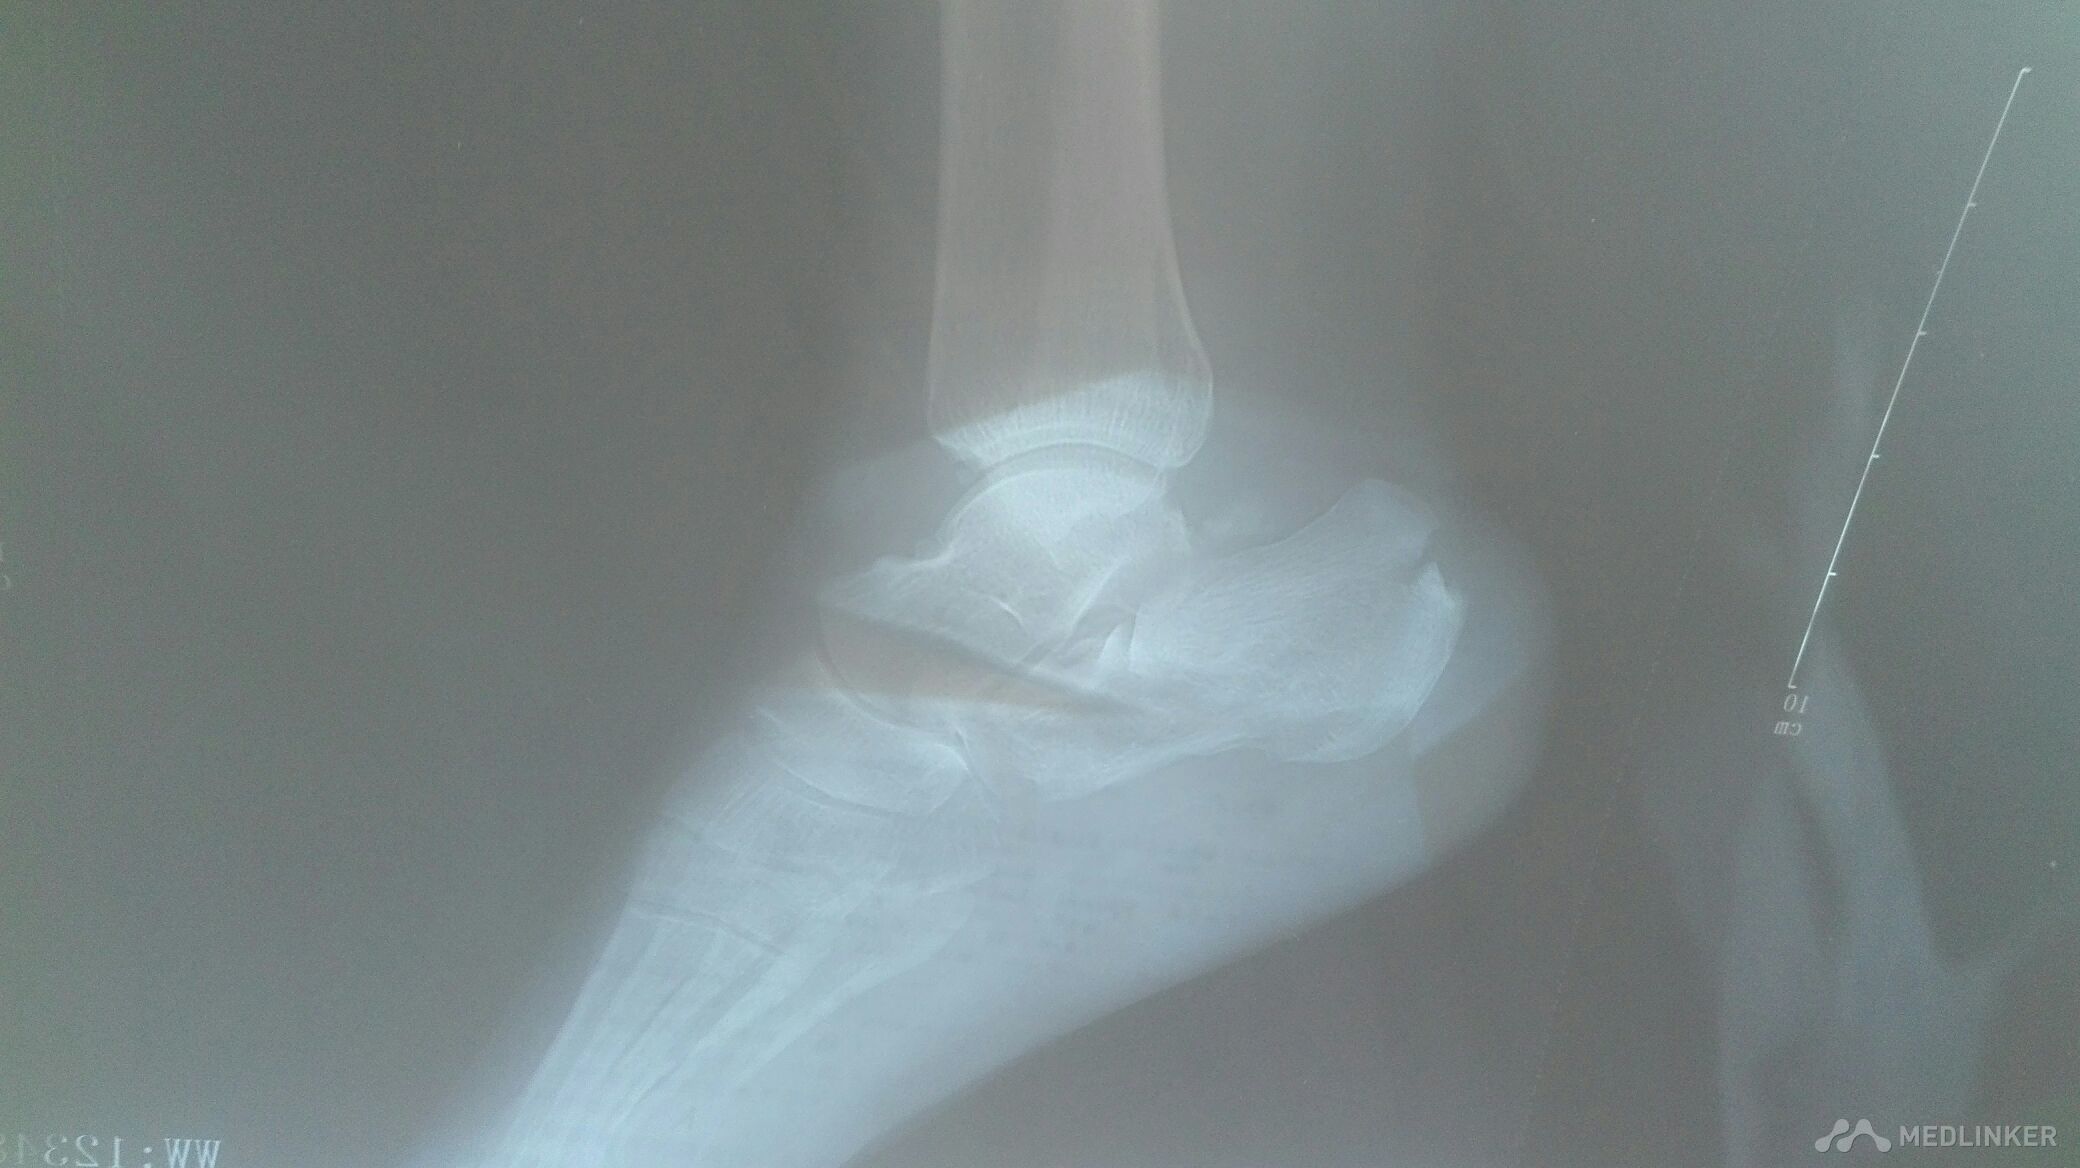

跟骨骨折